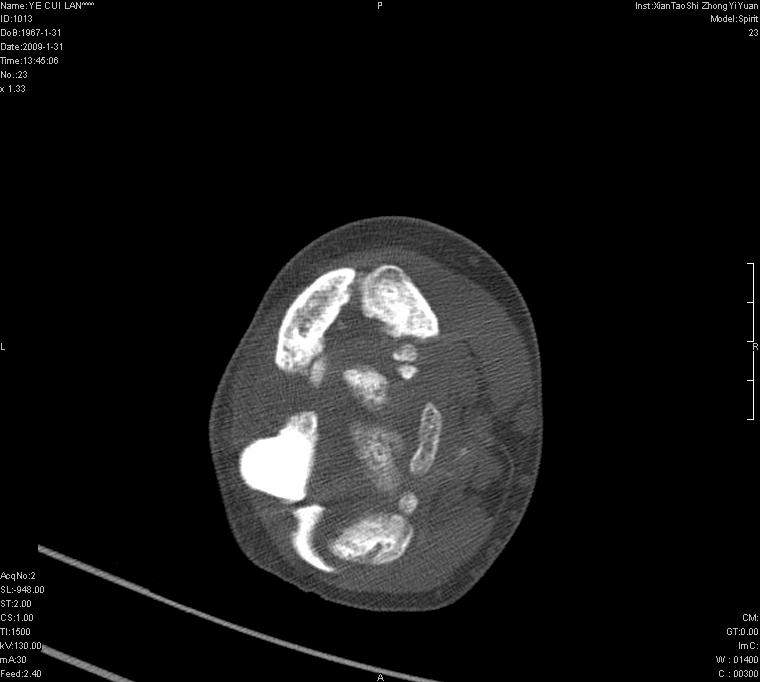

以下是引用王明发在2009-2-9 11:53:00的发言:[br]支持夏科氏关节,必要时行脊髓mri检查 [br]夏科氏关节是指由于某些神经系统疾病引起的关节病变,也被称为神经性关节炎。常见病因有脊髓痨、脊髓空洞症等。原发的神经病变可以造成关节深部感觉障碍,对于关节的震荡、磨损、挤压、劳倦不能察觉因而也不能自主地保护和避免,而神经营养障碍又可使修复能力低下,使病人在无感觉状态下造成了关节软骨的磨损和破坏,关节囊和韧带松弛无力,易形成关节脱位和连枷关节。关节面的破坏和骨赘的脱落变成关节内游离体。关节外形饱满肿胀,内有出血和渗出。这种病早期并无疼痛,不易被病人重视,仅表现为关节肿胀、无力、活动过度、动摇不稳。关节肿胀、无痛、活动范围超常是本病的重要特征。x光片可见有关节骨端广泛破坏、硬化或呈奇异形态,骨赘形成,关节间隙不规则或增宽,周围软组织钙化、关节内游离体、骨碎片等。结合x光片及临床症状,病人又有神经系统原发病症,即可确诊

以下是引用hhcckk在2009-2-9 14:31:00的发言:[br]夏科关节的六大表现[br]1.关节软组织肿胀。[br]2.关节的脱位与半脱位。[br]3.关节内的游离体。[br]4.关节面硬化,新骨形成。[br]5.骨质萎缩与破坏。[br]6.关节结构的紊乱。[br]加上患者无明显疼痛,诊断的把握性比较大